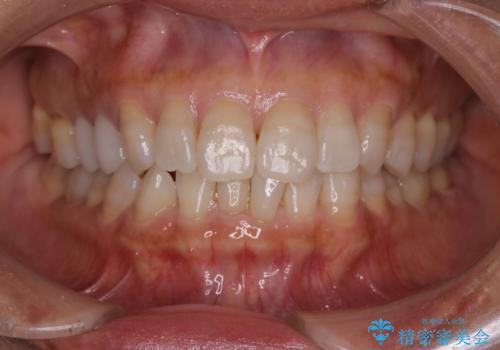

【インビザライン】下前歯だけを治したい

- 下前歯のがたつきにより唇を巻き込んでかんでしまい痛いため矯正をしたいという主訴で来院されました。今回は下顎前歯のみという強い希望があり、下顎のみのインビザライン矯正をしました。

叢生を改善するためのスペースはIPRと拡大を行いました。治療後は唇を巻き込んでしまう主訴が改善し、ご満足していただけました。